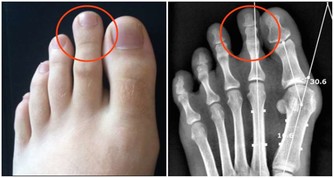

大腸癌早期無症狀,或症狀不明顯,僅感不適、消化不良、大便潛血等。隨著癌腫發展,症狀逐漸出現,表現為大便習慣改變、腹痛、便血、腹部包塊、腸梗阻等,伴或不伴貧血、發熱和消瘦等全身症狀。腫瘤因轉移、浸潤可引起受累器官的改變。大腸癌因其發部位不同而表現出不同的臨床症狀及體徵。

其實,痔瘡、肛裂、直腸癌都會出現便血的症狀,症狀相似,很容易誤診。也造成了許多患者在出現肛腸問題時,當做痔瘡自行治療,致使許多肛乳頭瘤、直腸息肉、甚至直腸腫瘤患者錯過治療的最佳時機。

所以當發現大便帶血時,最好去醫院外科做直腸指診,可以在很大程度上發現是否患有直腸癌。若大便中有血、黏液,大便習慣改變,腹瀉與便秘交替出現,最好去做結腸鏡,千萬不要有僥倖心理。